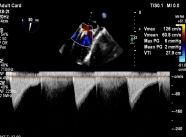

【图片1:术前超声图】

病例1为典型退行性二尖瓣脱垂(DMR),术前超声提示外交界瓣叶明显脱垂,反流程度达重度(4+),伴随活动后气促等心衰症状。由于病变位于“红区”,瓣叶结构复杂、对合不稳定,属于TEER治疗中的高难度类型。